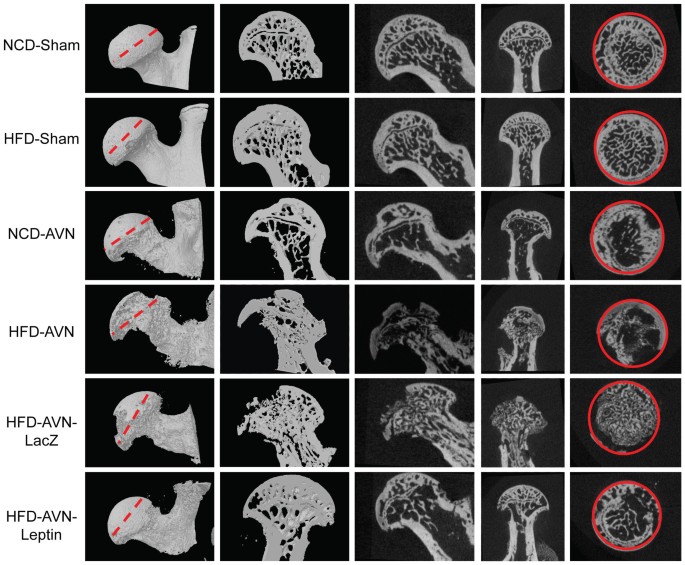

Necrosis is a general term that means a cell has died. Avascular necrosis of bone (avn) occurs as two main variants, local and systemic. # surgical neck of humerus b.

Due to necrosis of the cells of bone marrow and bone fibrovascular, reactions with hyperemia can be delineated. • avascular necrosis = avascular and aseptic bone necrosis • ischemic necrosis = necrosis of epiphyseal + subarticular bone • bone infarction = necrosis of metaphyseal + diaphyseal bone. These medications that boost bone density could lead to osteonecrosis of the jaw. # neck of femur e.